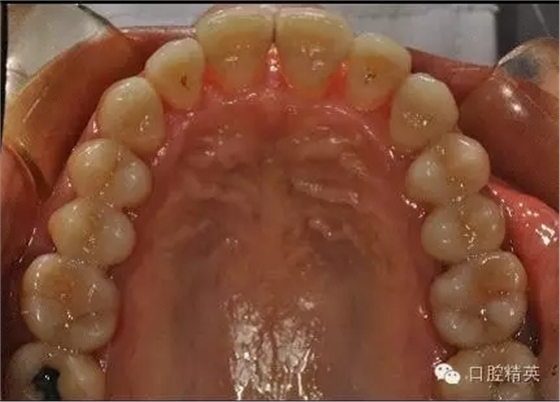

齦下刮治術(shù)(subgingival scaling),即根面平整術(shù)(root planing),是用比較精細(xì)的齦下刮治器刮除位于牙周袋內(nèi)根面上的牙石和菌斑。做齦下刮治時(shí),醫(yī)生會(huì)使用一些專用去除袋內(nèi)結(jié)石的器械,刮除袋內(nèi)結(jié)石、細(xì)菌和受細(xì)菌感染組織。由于進(jìn)行該項(xiàng)操作需將器械伸入袋的深部組織內(nèi),既要刮盡齦下牙石(有時(shí)還要刮除牙根表面的壞死組織),又要盡量避免多損傷牙周組織。這就需要有較高的技巧,只有經(jīng)過(guò)專門訓(xùn)練的專業(yè)技術(shù)人員才能完成。

治療后:炎癥得到控制,牙周袋已消除,松動(dòng)度有所改善。